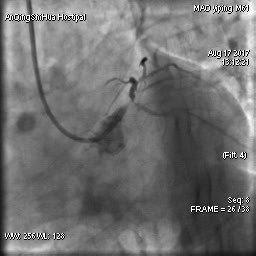

毛先生的血管在心臟左主干體部及分叉部都出現(xiàn)嚴重狹窄,僅一絲血流通過,前降支的血流已明顯減慢。難怪日常步行都會引起心絞痛,毛先生隨時都可能心臟驟停。

術(shù)前 心臟左主干末端嚴重狹窄